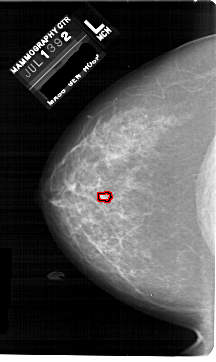

A_1742_1.LEFT_CC

LEFT_CC LINES 6871 PIXELS_PER_LINE 4096 BITS_PER_PIXEL 12 RESOLUTION 43.5 OVERLAY

FILE: A_1742_1.LEFT_CC.OVERLAY

TOTAL_ABNORMALITIES 1

ABNORMALITY 1

LESION_TYPE MASS SHAPE LOBULATED MARGINS CIRCUMSCRIBED

ASSESSMENT 4

SUBTLETY 2

PATHOLOGY BENIGN

TOTAL_OUTLINES 1

BOUNDARY